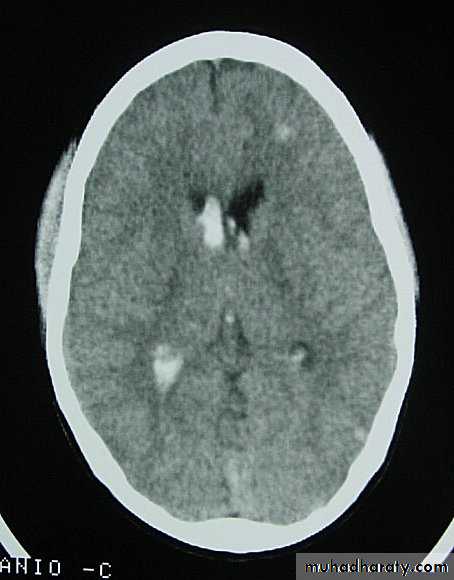

5. Hydrocephalus

a. Acutely due to obstruction of CSF outflow due to intraventricular blood.

b. Delayed post-traumatic communicating hydrocephalus due to impaired CSF reabsorption following traumatic subarachnoid haemorrhage

Intraventricular blood can lead to Hydrocephalus